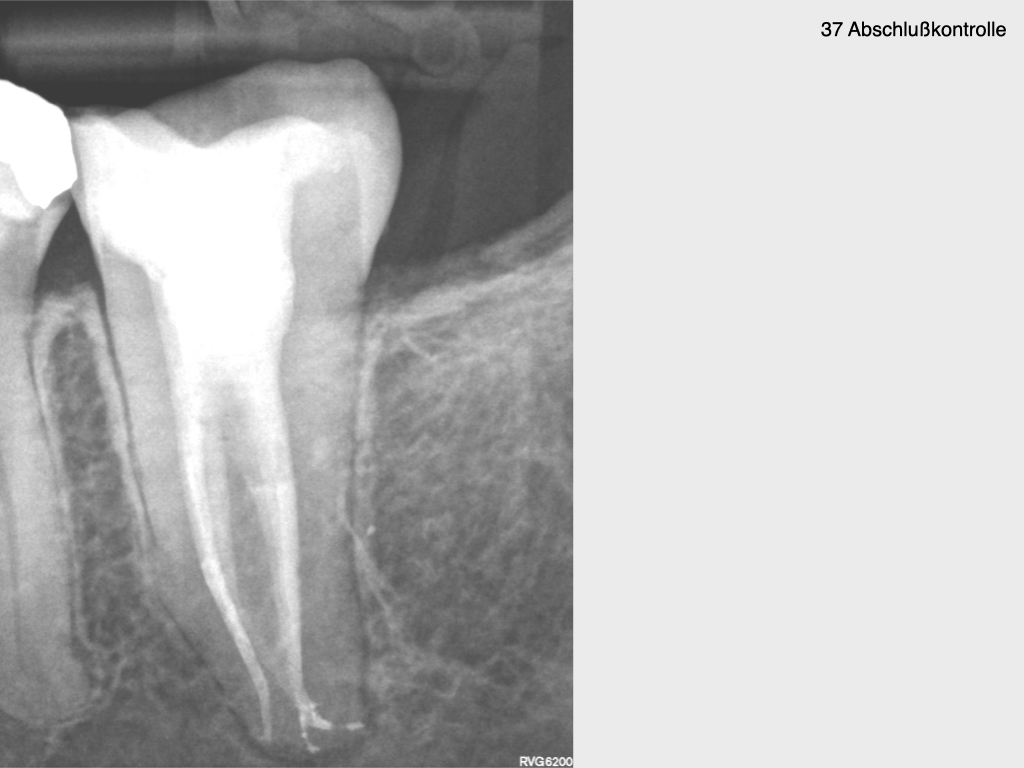

Krampf und Kampf